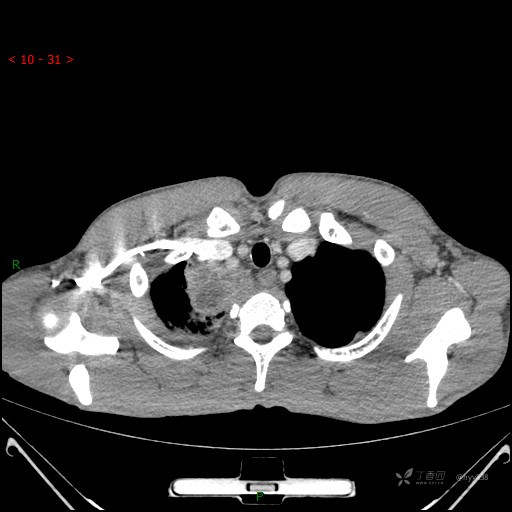

辅助检查:CT

静脉期